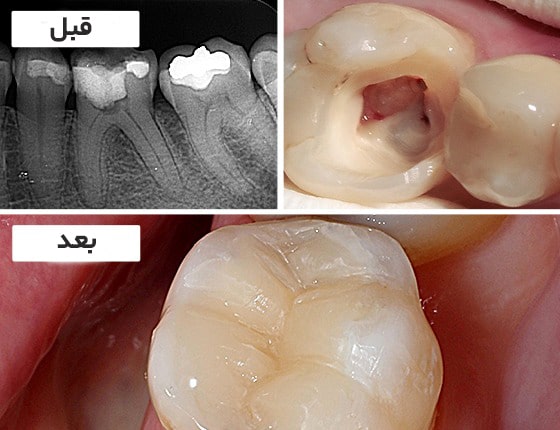

در برخی از موارد، دندان بعد از عصب کشی به دلیل آسیب دیدگی شدید نیاز به روکش دندان دارد. لازم به ذکر است این اتفاق بیشتر در دندان های خلفی و دندان های دارای پوسیدگی عمیق مشاهده می شود به همین دلیل هزینه روکش دندان با توجه به نوع ماده متغیر خواهد بود.

سطح پوسیدگی دندان

بازسازی دیواره دندان